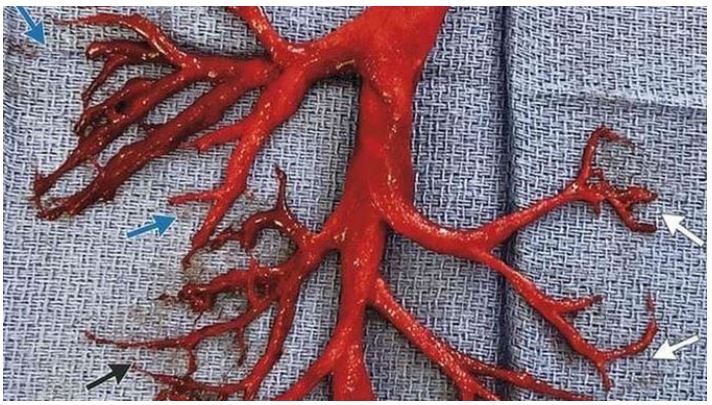

Researchers from Germany have conducted the world's first-ever postmortem study on a corpse that prior to death had been "vaccinated" for the Wuhan coronavirus (Covid-19). They found that every single organ of the now-deceased person's body had become infested with spike proteins due to the jab.

Researchers later found that the patient's entire body had become overrun with high viral RNA loads, also known as vaccine-induced spike proteins. The man was clearly killed by the jab.